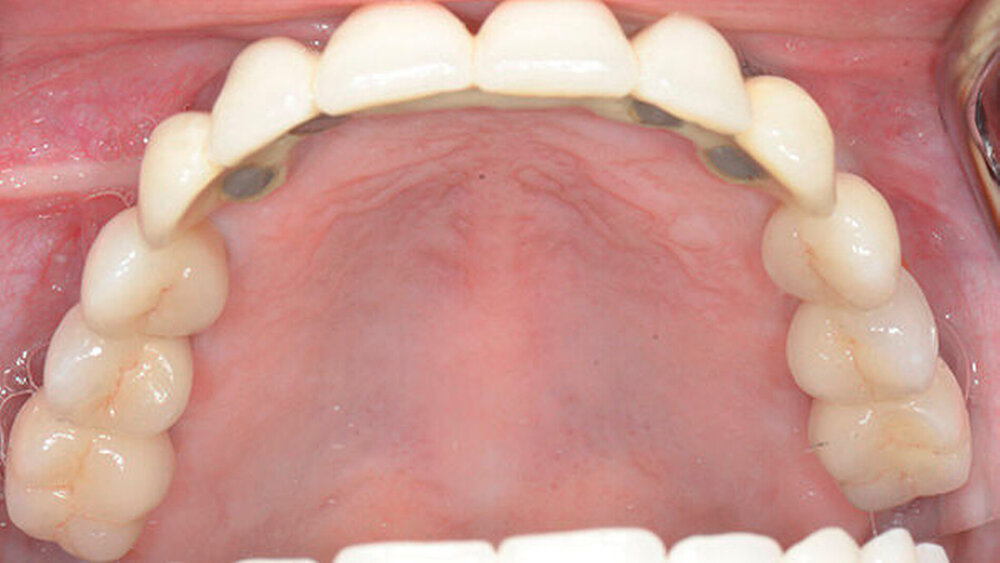

Daher mussten auch die Seitenzähne im Oberkiefer und teilweise im Unterkiefer entfernt und mit Implantaten ersetzt werden. Dies erfolgte unter anderem unter Einsatz von navigationsgestützten Techniken. Im Seitenzahnbereich des Oberkiefers musste eine Sinusaugmentation mit Knochen durchgeführt werden. Dabei wurde mit allen Vorsichtsmaßnahmen vorgegangen, die nach einer Bestrahlung des Knochens zu treffen sind.

Bis zur letztendlich verbleibenden festsitzenden Versorgung der Implantate mit Kronen musste die Patientin eine herausnehmbare Prothese mit Gaumenabdeckung tragen, die sie als junge Mutter sehr belastete. Umso glücklicher ist die Patientin nun über ihre vollständige prothetische Rehabilitation.